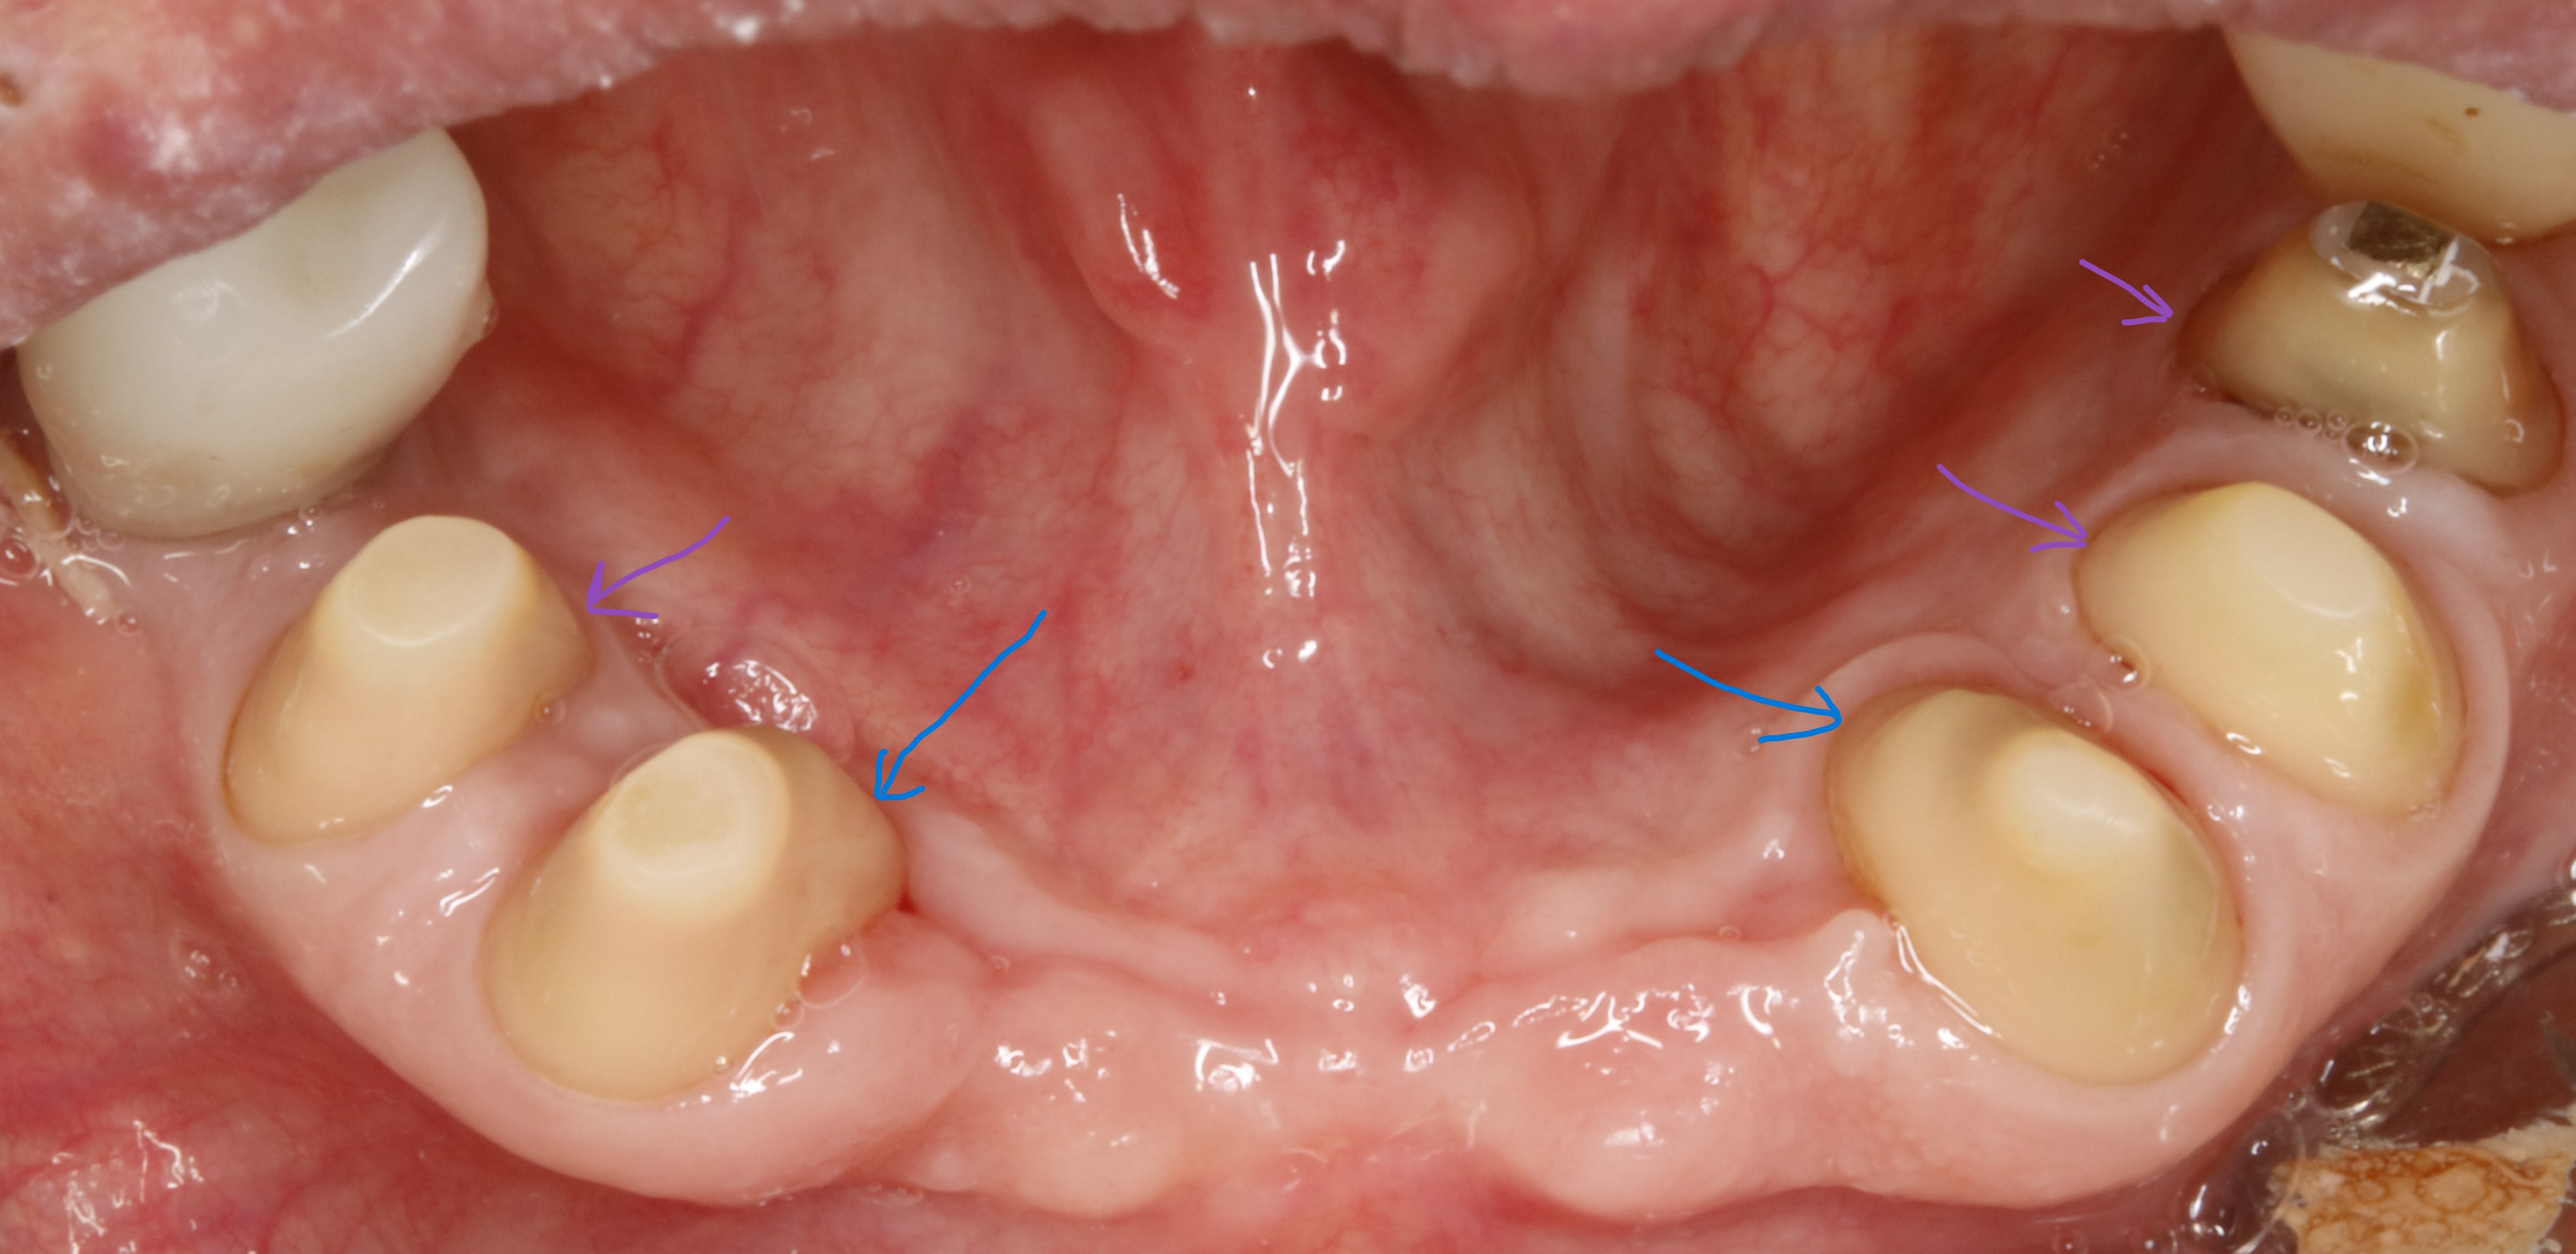

Daryl on va parler de la conicité , et tu vas voir qu ici par exemple eh bien ce n est pas si conique que ça , c est d'ailleurs pour ça que le prov tient tout seul.

ici , on doit faire un bridge canine canine .les autres dents sont juste des piliers accessoires .

dejà , le bridge canine +accessoires par sa forme de fer à cheval est auto stable puisque les forces principales viennent d en haut et de devant .

les canines etant les plus costaudes , on va donc essayer de ne pas trop les fracasser et les choisir comme axe d insertion . ce sera donc notre axe de taille directeur . cet axe etant bien sur l axe moyen (ou commun) entre les deux .

donc on commence par tailler les canines en mettant de dépouille .

devant ( en vestibulaire ) on a vu que c etait auto stable , à condition bien sur de laisser la place au montage des dents . donc la courbure de devant dépend de la forme cingulaire des dents du haut .eh oui :-)

alors maintenant derrière c est diffèrent , avec la langue , ce n est pas du tout auto stable , et vu que devant c est assez incliné , il va falloir trouver de la rétention . et y en a pas beaucoup et elle se trouve juste au depart de la dent . elle est si précieuse qu une fois taillée , on y reviendra plus jamais .

ce sera notre axe de rétention de référence pour tout le bridge .

et on ne peut pas dire qu il y ait de la conicité entre les deux .

voir les traits bleus sur la photo , sauf si comme dans mission impossible , elle disparait .:-)

arrive maintenant le congé .

on a vu qu en vest , du fait que ce soit penché à cause des dents du haut , ce serait bien de rajouter une opposition avec la face linguale .

donc au pied si on pouvait rentrer un peu tout en redressant ce serait pas mal .

ben voilà , il sert à ca le congé , le voilà . à faire la férule de PP :-)

le congé doit donc servir à réduire la conicité .

c est pour ca qu il doit être fait APRES la face linguale .

puisque que peuchère , la face linguale étant limitée , on s adapte à elle et on parallélise à mort , enfin on essaye .

traits rouges sur photos .

bon maintenant on va s occuper des autres .

les autres , accessoires , faut qu elles suivent le mouv s agirait pas quelles n en face qu à leurs tête . .

elles sont là pour s intégrer au bridge et si possible en augmentant la stabilisation .

ce qui veut dire qu il ne faudrait pas quelles soit plus ou moins rétentives que les canines .

donc on les parallélise aux canines sur les faces vest .

traits verts sur photo

le rapport le voilà , je remets ici la photo du prov au bout de 3 mois , avec les traits orange .

de toute évidence il y a des faces d usure à gauche qu il n y a pas à droite .

donc même sans parler pb occlusal , si je veux faire la prothèse , il faudra au minimum que je sois homothétique à ces pistes .

ce qui va m obliger à rentrer les moignons en lingual . pcq de toute évidence , lui il n a qu une envie c est d aller à gauche . et s il y est allé avec les prov , il y retournera avec les vrais

maintenant regardes bien la photo vue de haut que je remets .tu le vois le trait gris ?

c est l alignement de la ligne de crête . et cà c est fondamental pcq c est ce qui préfigure la courbe de Wilson et Monson .

bref , le fait d aligner les sommets va t obliger à incliner les moignons si besoin .

elle vient de là la conicité du bordel global . :-)

et c est là que tu ressors le congé . c est en faisant les congés en vest que tu rentres le pied des dent et donc que tu réduis la conicité .

conicité , je le rappelle , par exemple , entre vest de 44 et de 34 , hein , faut pas l oublier ça . sinon c est la contre dépouille direct .

mais tu comprends aussi tres vite que plus ton congé est large plus tu perds de la rétention , puisque si tu prends une grosse fraise , en quart de rond , toute la partie arrondie va te faire une découpe horizontale qui elle ne te servira à rien quand à la rétention par contre elle te servira à bien niquer la dent .

moralité le gros congé ça ne peut pas aller .

a la limite tu peux faire un double congé en espérant rajouter un peu de partie verticale .

ici sur les canines ça nous arrange pour avoir des dents plus fines .

traits noirs sur la photo .